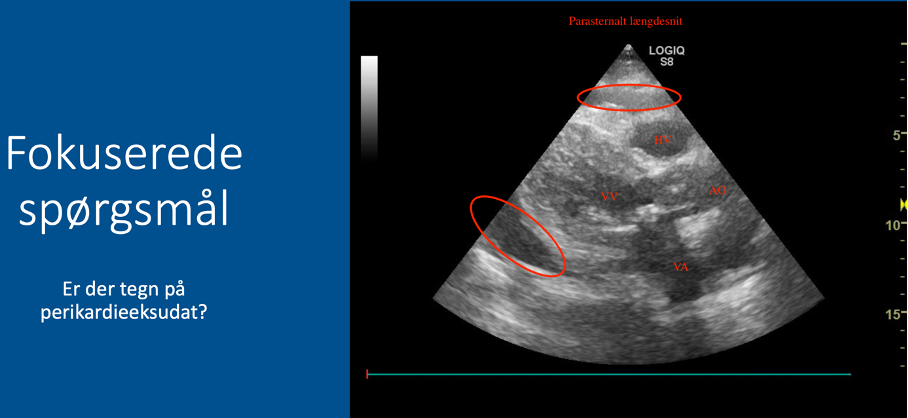

Fokuserede spørgsmål (FHUS):

* Perikardieeffusion: ja/nej?

Q